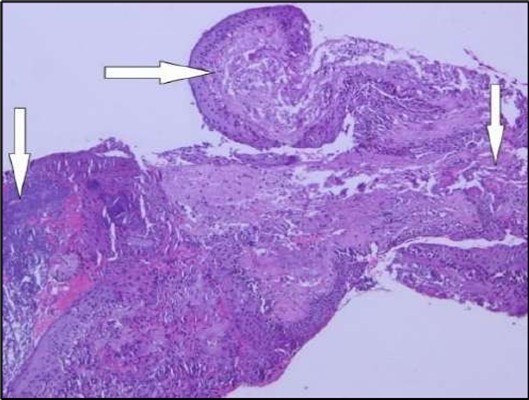

Two weeks post-surgery, the left eye showed significant healing, with a small conjunctival granuloma and vascularization at the ulcer margins. The cornea was clear with a central leading edge nasally, deep and quiet anterior chamber and clear lens. VA 6/6 bilaterally and IOP normal. Histopathology of excised conjunctiva showed non-keratinized squamous epithelium with superficial erosions, stromal elastosis, hemorrhage, and inflammatory infiltration, but no signs of granulomatous disease, malignancy, or viral evidence, findings consistent with idiopathic localized inflammatory process. The patient reported significant relief and satisfaction post-surgery, resuming normal activities. Treatment continued with oral prednisolone 25 milligrams every other day, tobramycin-dexamethasone ointment twice daily, and preservative-free artificial tears four times daily Figure 4, Figure 5a, Figure 5b, Figure 5c, Figure 5d.

Figure 5a.OS, Hematoxylin and eosin (H&E) stained section of the corneal specimen demonstrating full-thickness epithelial loss with underlying stromal necrosis.

Histopathological examination revealed a dense infiltration of CD138-positive plasma cells within the excised conjunctival tissue (Figure 5b, Figure 5c, Figure 5d). This finding supports an antibody-mediated immunopathogenesis in Mooren’s ulcer, consistent with Type II and Type III hypersensitivity mechanisms described in the literature 20, 21. The prominent presence of CD138- positive plasma cells provide a clear pathological rationale for conjunctival resection, as excision of the immunologically active perilimbal conjunctiva effectively removes the local 'factory' of autoantibodies that drive corneal stromal destruction, thereby halting ongoing tissue damage 21.